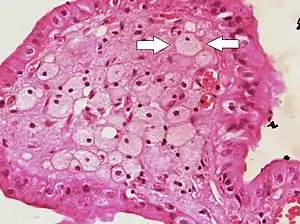

![]() Foam cells (one indicated by arrows) visible in the finger-like projections into the gallbladder lumen in a case of cholesterolosis | |